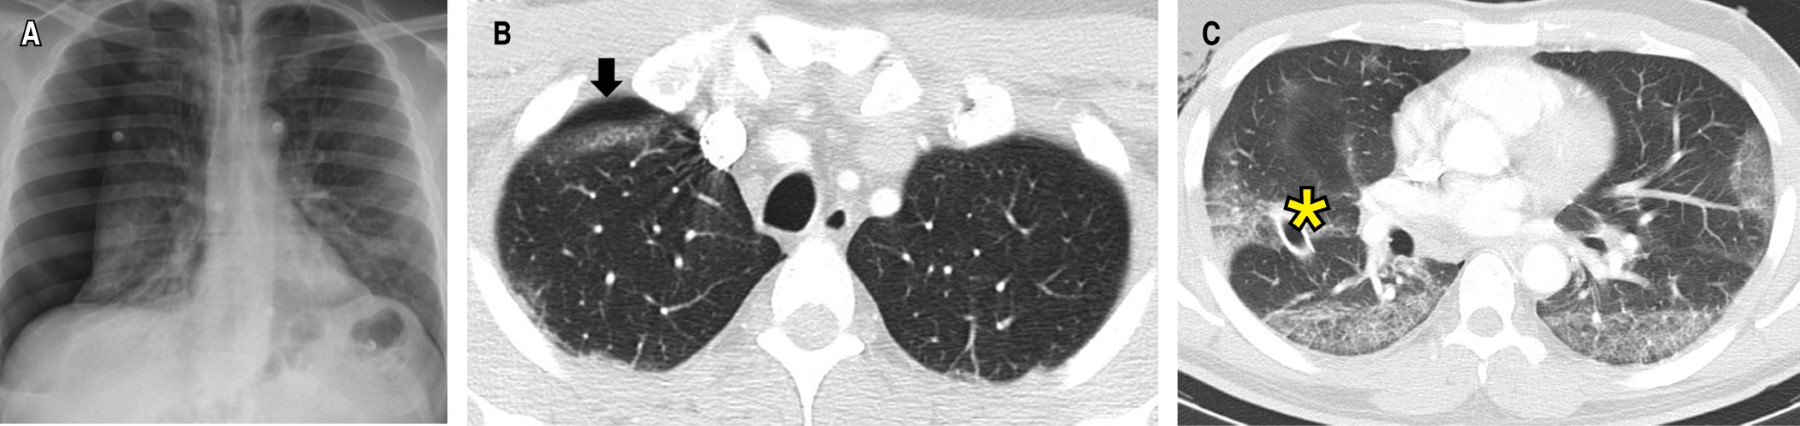

La radiografía de tórax demostró un neumotórax derecho con colapso de 50% del hemitórax ipsilateral (Figura 1A), que requirió manejo con toracostomía cerrada derecha y expansión completa pulmonar en los controles radiográficos. La angiotomografía (angio-TC) de tórax descartó tromboembolismo pulmonar (TEP) y evidenció opacidades en vidrio esmerilado (OVE) bilaterales, de distribución periférica, subpleural, con engrosamiento septal interlobulillar y enfisema subcutáneo derecho (Figuras 1By C). Se consideró neumonía por COVID-19, y su manejo consistió en dexametasona intravenosa (IV) de acuerdo al ensayo RECOVERY,20 oxígeno (FiO2 32%) y analgesia. A las 72 horas se retiró el tubo de tórax. Los laboratorios de control mostraron disminución de los marcadores de severidad, con egreso a los siete días de estancia hospitalaria. En el seguimiento a los tres meses (Tabla 1), la puntuación de la escala de disnea modificada del Medical Research Council (mMRC) fue de cero, sin alteraciones en las pruebas de función pulmonar, con OVE residuales en la tomografía control.